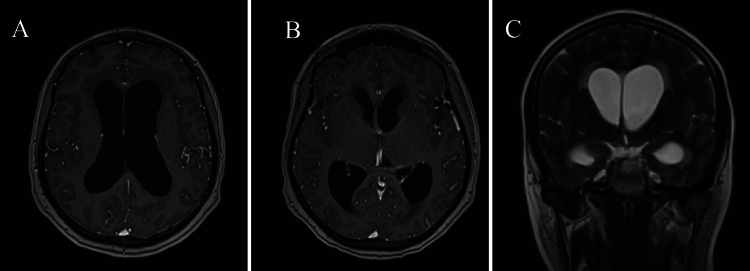

Observations: A 47-year-old female presented with a 3-month history of short-term memory disturbances, ultimately leading to loss of consciousness. Neuroimaging revealed symmetrical biventricular hydrocephalus accompanied by periventricular interstitial edema. A lumbar puncture indicated lymphocytic-dominant pleocytosis and reduced glucose levels. During the endoscopic approach, significant stenosis of the foramen of Monro was noticed and monroplasty and septostomy were performed. Pathological examination revealed granulomatous inflammation. At the 1-year follow-up, the patient demonstrated significant clinical and radiological improvement, with resolution of symptoms and hydrocephalus.

Abstract Image